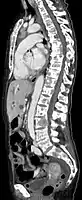

Scanner sagittal reconstruit, représentation dans la fenêtre osseuse. Comme la patiente avait des métastases dans toutes les régions du corps, elle ne pouvait pas lever les bras pour l'examen, ce pourquoi les mains sont présentées.

Scanner sagittale, parties molles. Outre les métastases dans la colonne vertébrale, qui envahissent en partie le canal médullaire vers l'arrière, métastases aussi dans le sternum. Plus des métastases dans le foie.